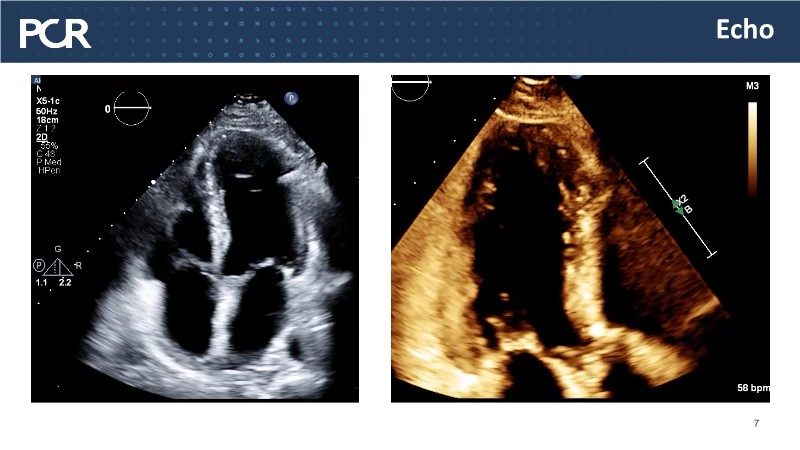

- To reflect about optimal use of dedicated device in calcified coronary lesions

- To assess how IC imaging of calcified lesions will improve PCI results and patients outcomes